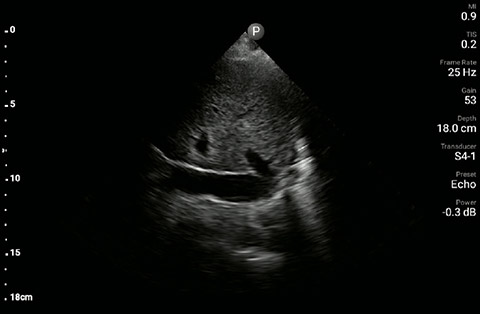

The patient had reduced LV systolic function without new or severe valvular pathology, a dilated, non-collapsing IVC, and diffuse B lines (left greater than right) on lung ultrasound imaging.

Apical 4-chamber